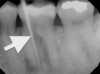

When a patient presents for restorative treatment and reports that a tooth is asymptomatic, a dentist may assume that the pulpal and periradicular diagnosis is within normal limits and hence may skip the above objective clinical tests, with the possible exception of taking a radiograph. However, using only a dental radiograph to determine the etiology of tooth pain and the pretreatment pulpal and periradicular status may lead to a pulpal and periradicular misdiagnosis (Figure 3). Therefore, a clinician must perform all five objective tests to obtain an accurate pretreatment pulpal and periradicular diagnosis.

Fig 3. Determining a diagnosis with a radiograph only can lead the clinician to treat tooth No. 29 because of the distal decay. However, if the proper diagnostic tests are performed on tooth No. 29, it should reveal the pulp tested necrotic and it is tooth No. 30 that has a symptomatic irreversible pulpitis.

Figure 3